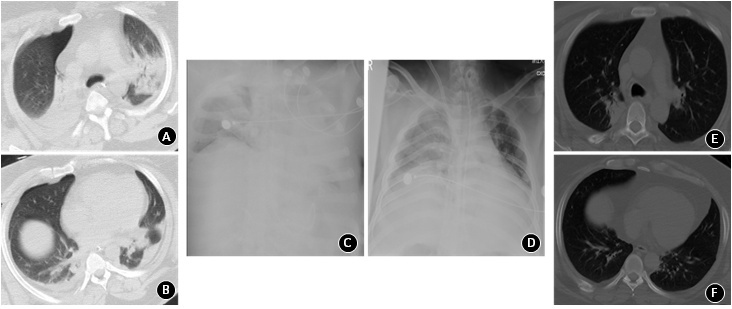

1 资料与方法患者,男性,38岁,重度肥胖(体重指数41.6),否认既往疾病史,系安全带坐在副驾驶位,过隧道后撞在树上致“胸部、右手臂、右髋疼痛1 h余”于2022年8月24日13时送入当地医院。主要诊断“肺挫伤,呼吸衰竭”,给予机械通气、纤维支气管镜下吸痰,患者血氧饱和度一度好转后再次恶化,查螺旋CT肺动脉造影排除肺栓塞, 于伤后42 h转入本院急诊监护室。当时患者处于深度镇静状态,体温37.5℃,呼吸:18次/min脉搏:100次/min,血压:130/80 mmHg (1 mmHg=0.133 kPa),血氧饱和度92%。经口气管插管接呼吸机通气,容量控制模式, 潮气量: 480 mL, 氧体积分数: 70%, 呼吸末正压: 8 cmH2O (1 mmH2O=0.098 kPa), 气道内吸出大量黄白色黏痰,两肺呼吸音粗,可闻及少量哮鸣音,右髋关节屈曲,内旋内收位,右上臂畸形,右上腹可及一约3 cm×3 cm包块,氧合指数120。测白细胞15.2×109/L,中性粒细胞12.31×109/L,淋巴细胞数1.5×109/L,血小板158×109/L,C反应蛋白52.6 mg/L,白介素-6 20.6 pg/mL。主要诊断:(1)多发伤(ISS 38分,MAIS 5分)①两侧肺挫伤,右侧3~7后肋骨折,右侧气胸;②膈肌损伤,膈疝,腹壁疝;③右侧肱骨粉碎性骨折,右股骨头骨折,右髋关节后脱位;④胸3椎体骨折;(2)ARDS、下呼吸道感染。予肺保护通气、每日通便、控制肠内营养速度、深镇静、肌肉松弛维持呼吸机平台压≤30 mmHg, 腹内压<12 mmHg, 予纤维支气管镜下吸痰、经验性选用哌拉西林他唑巴坦4.5静滴/8 h抗感染、床边行右髋关节手法复位等处理。伤后第7天胸片显示两肺弥漫性渗出(如图 1-C)合并氧合指数持续低于80超过6 h,经过优化呼吸机、控制容量等综合救治措施仍不能改善严重低氧血症,予行VV-ECMO。第8天痰培养报告示为敏感肺炎克雷伯菌(klebsiella pneumoniae, KP)+铜绿假单胞菌+耐甲氧西林金黄色葡萄球菌(methicillin-resistant staphylococcus aureus, MRSA),调整抗感染方案为头孢他啶2.0静滴/8 h +利奈唑胺0.6静滴/12 h抗感染。治疗一周后,患者临床症状无显著好转,VV-ECMO参数不能下调,仍为黄黏痰液并发C反应蛋白与白介素-6升高,反复痰培养示为敏感KP。送检肺泡灌洗液mNGS,40 h后回报结果显示KP序列数7, 245, 673;毒力基因列表提示内有高毒力KP(iutA, rmpA2)[7];耐药基因列表显示含blaCTX-M、blaTEM、blaKPC (如图 2), 说明同时存在超广谱β-内酰胺酶(extended-spectrum β-lactamases ESBL)阳性KP,耐碳青霉烯类KP(carbapenem-resistant klebsiella pneumoniae CR-KP)与敏感KP[8-9],此时痰培养仍显示敏感KP。参照mNGS结果,予改头孢他啶为美罗培南2.0静滴/8 h +多黏菌素E 100万单位雾化/12 h。治疗2 d后患者氧合指数、炎症指标及肺部病变均好转(肺部病变变化如图 1 A-F),此后痰培养回报均为CR-KP,于第16天撤离VV-ECMO,美罗培南+多黏菌素使用10 d后停止。第21天行右肱骨固定术,第34天间歇脱离呼吸机,总机械通气时间40 d,第44天气管切开封堵(图 3总结了严重创伤后ARDS合并下呼吸道感染的诊治经过)。

| A与B.入科(D3)时两肺实变、左肺为著; C.ECMO上机前(D7)两肺弥漫性渗出; D.ECMO撤除前(D16)两肺渗出减少,左肺吸收明显; E与F.2月后肺部渗出基本吸收 图 1 肺部影像学变化 |